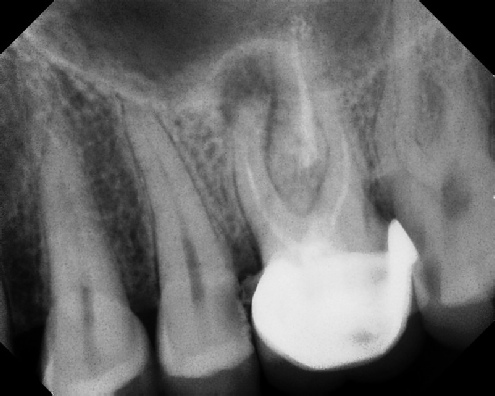

Root Canal Retreatment - Meriden 8 mos. recall Post-op Pre-op